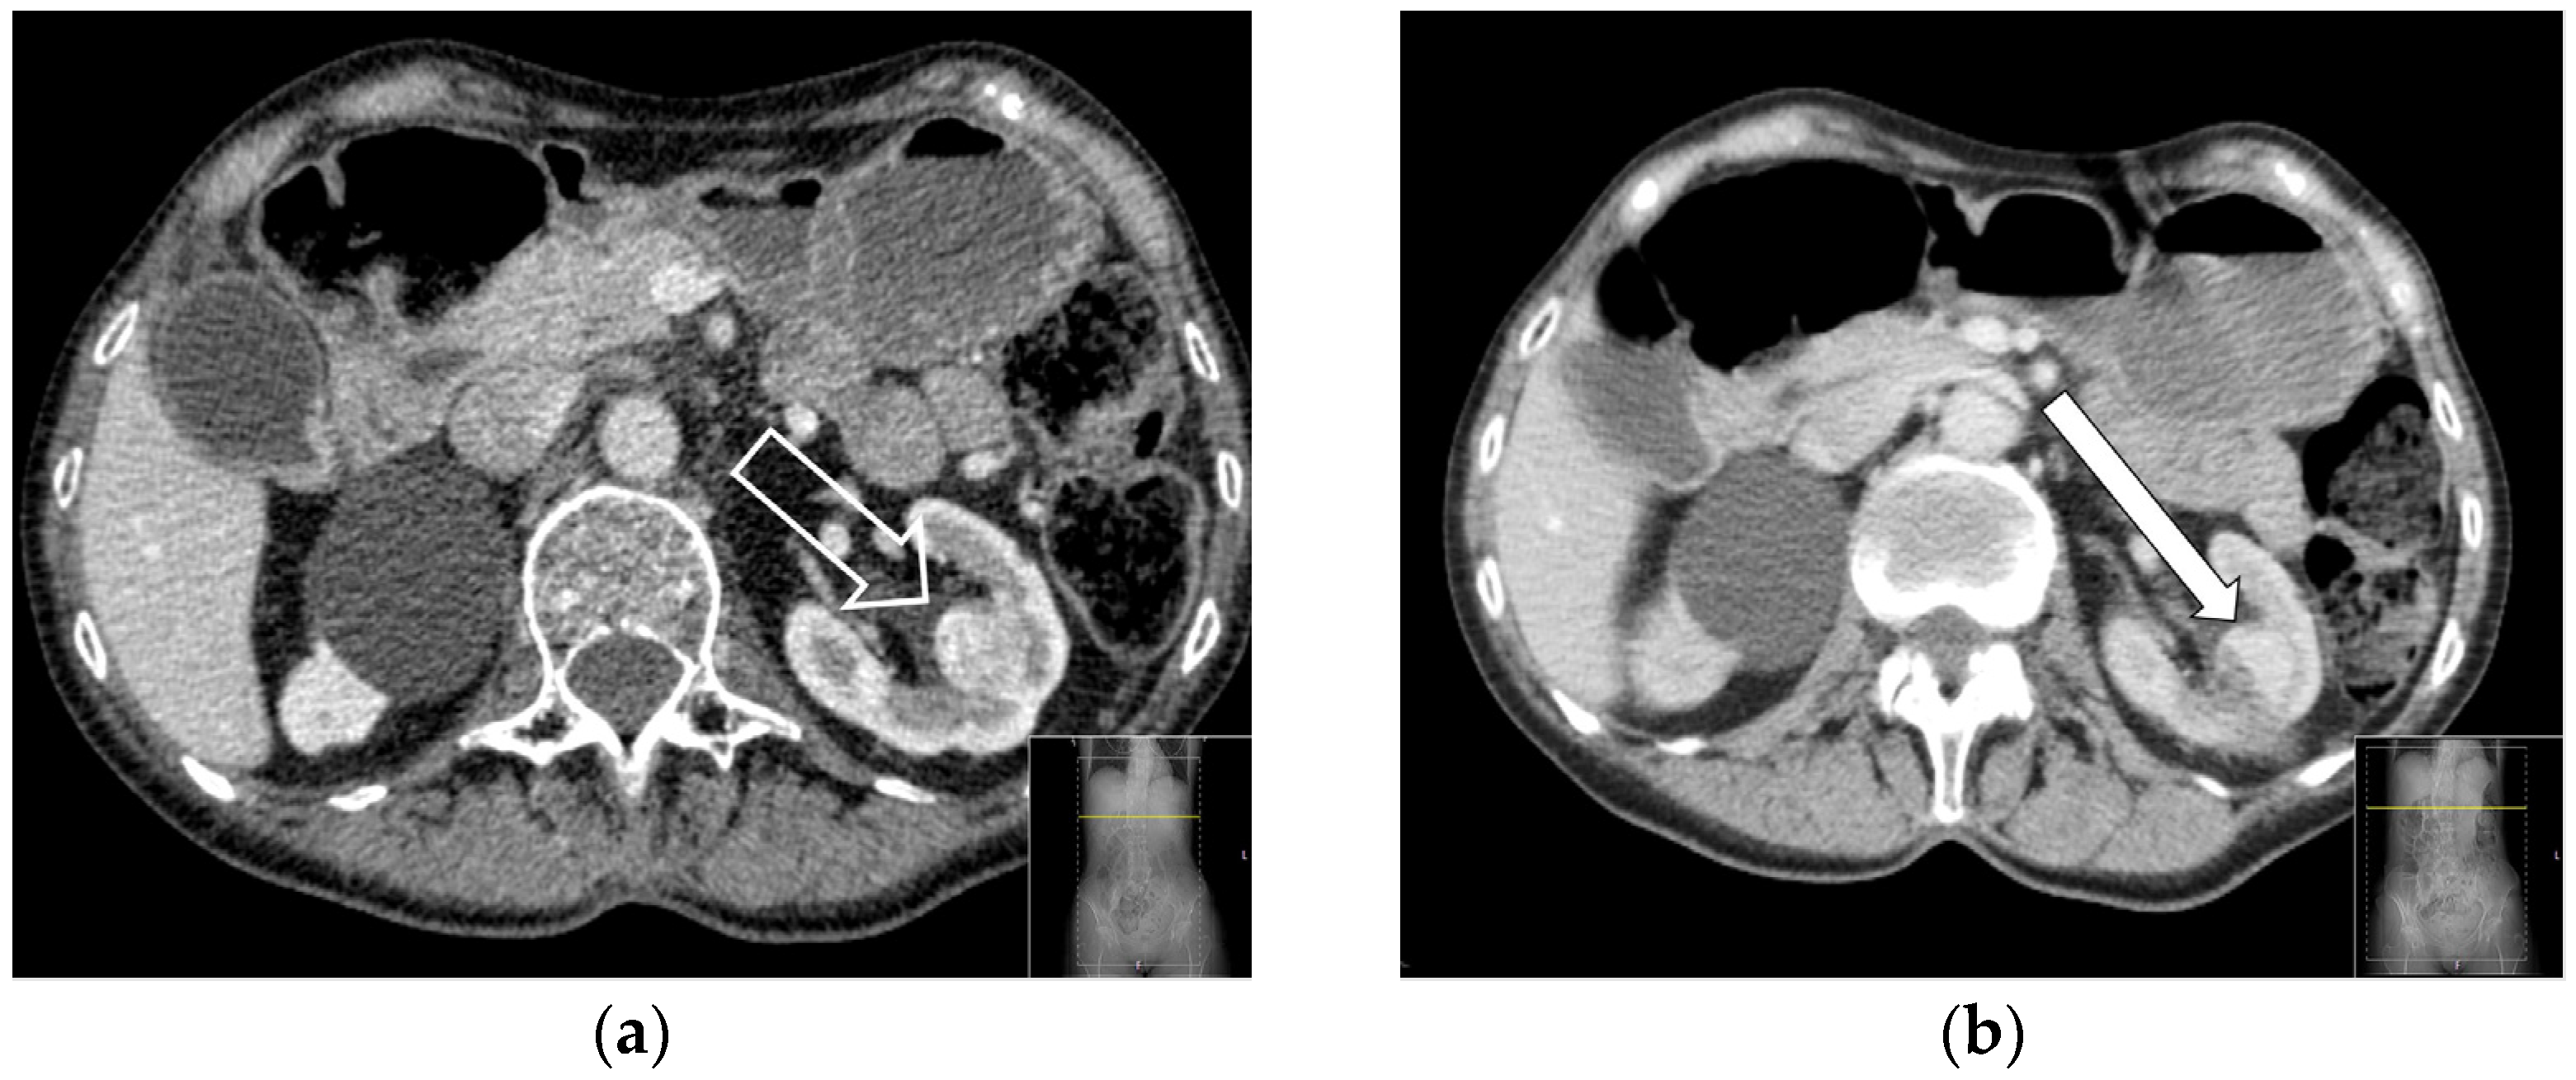

2.2. RFA—Technical Aspects